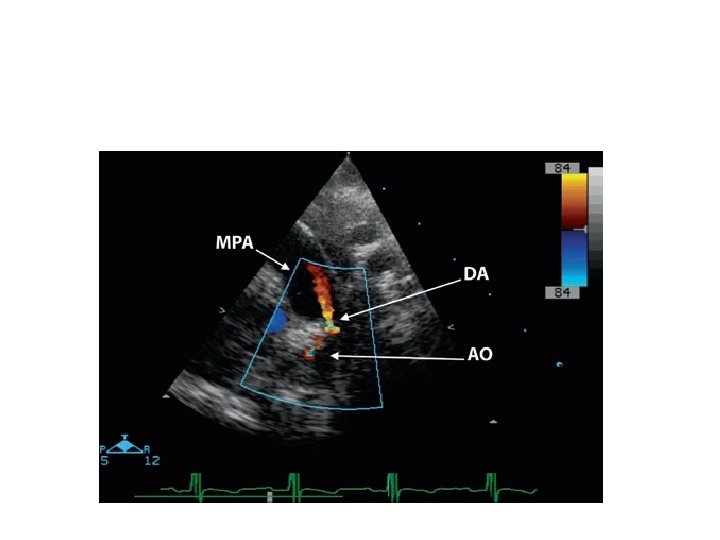

Pulmonary artery sling

• LPA arises as a branch of RPA • LPA courses in a position cephalad to right mainstem bronchus; between trachea & esophagus • Forms a "sling" and partially surrounds lower trachea • a/w tracheal stenosis • ONLY condition where a major vessel passes b/w trachea & esophagus